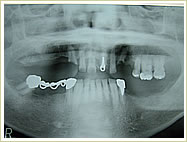

症例 57歳 女性 インプラント埋入数:6本 画像拡大

治療前 治療後